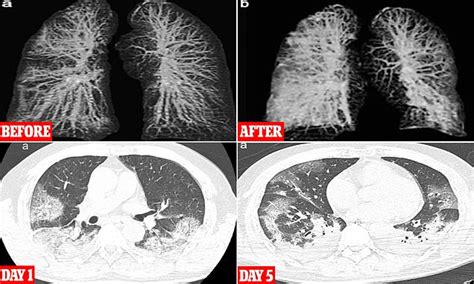

Shocking images reveal how the lungs of two Wuhan ...

Coronavirus: What X-rays and CT scans reveal about how ...

15 + Lung Images After Covid High Quality ImagesBoth lungs appearing white and opaque (versus black) on chest X-rays (called bilateral lung opacities on chest imaging). Here's what coronavirus can do to your lungs in mild-to-moderate, severe, and critical cases. Keith Mortman, the chief of thoracic surgery The hospital typically uses the CT imaging technology that produced the video for cancer screenings and to plan surgeries.